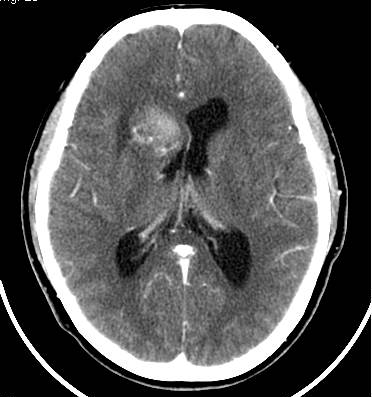

病史不详,右侧尾状核病灶出血,第二天做了颅脑ct增强,请大家帮忙看看如何诊断,谢谢!

增强:前部还是原先出血病灶,后方强化的似为异常的血管显影。